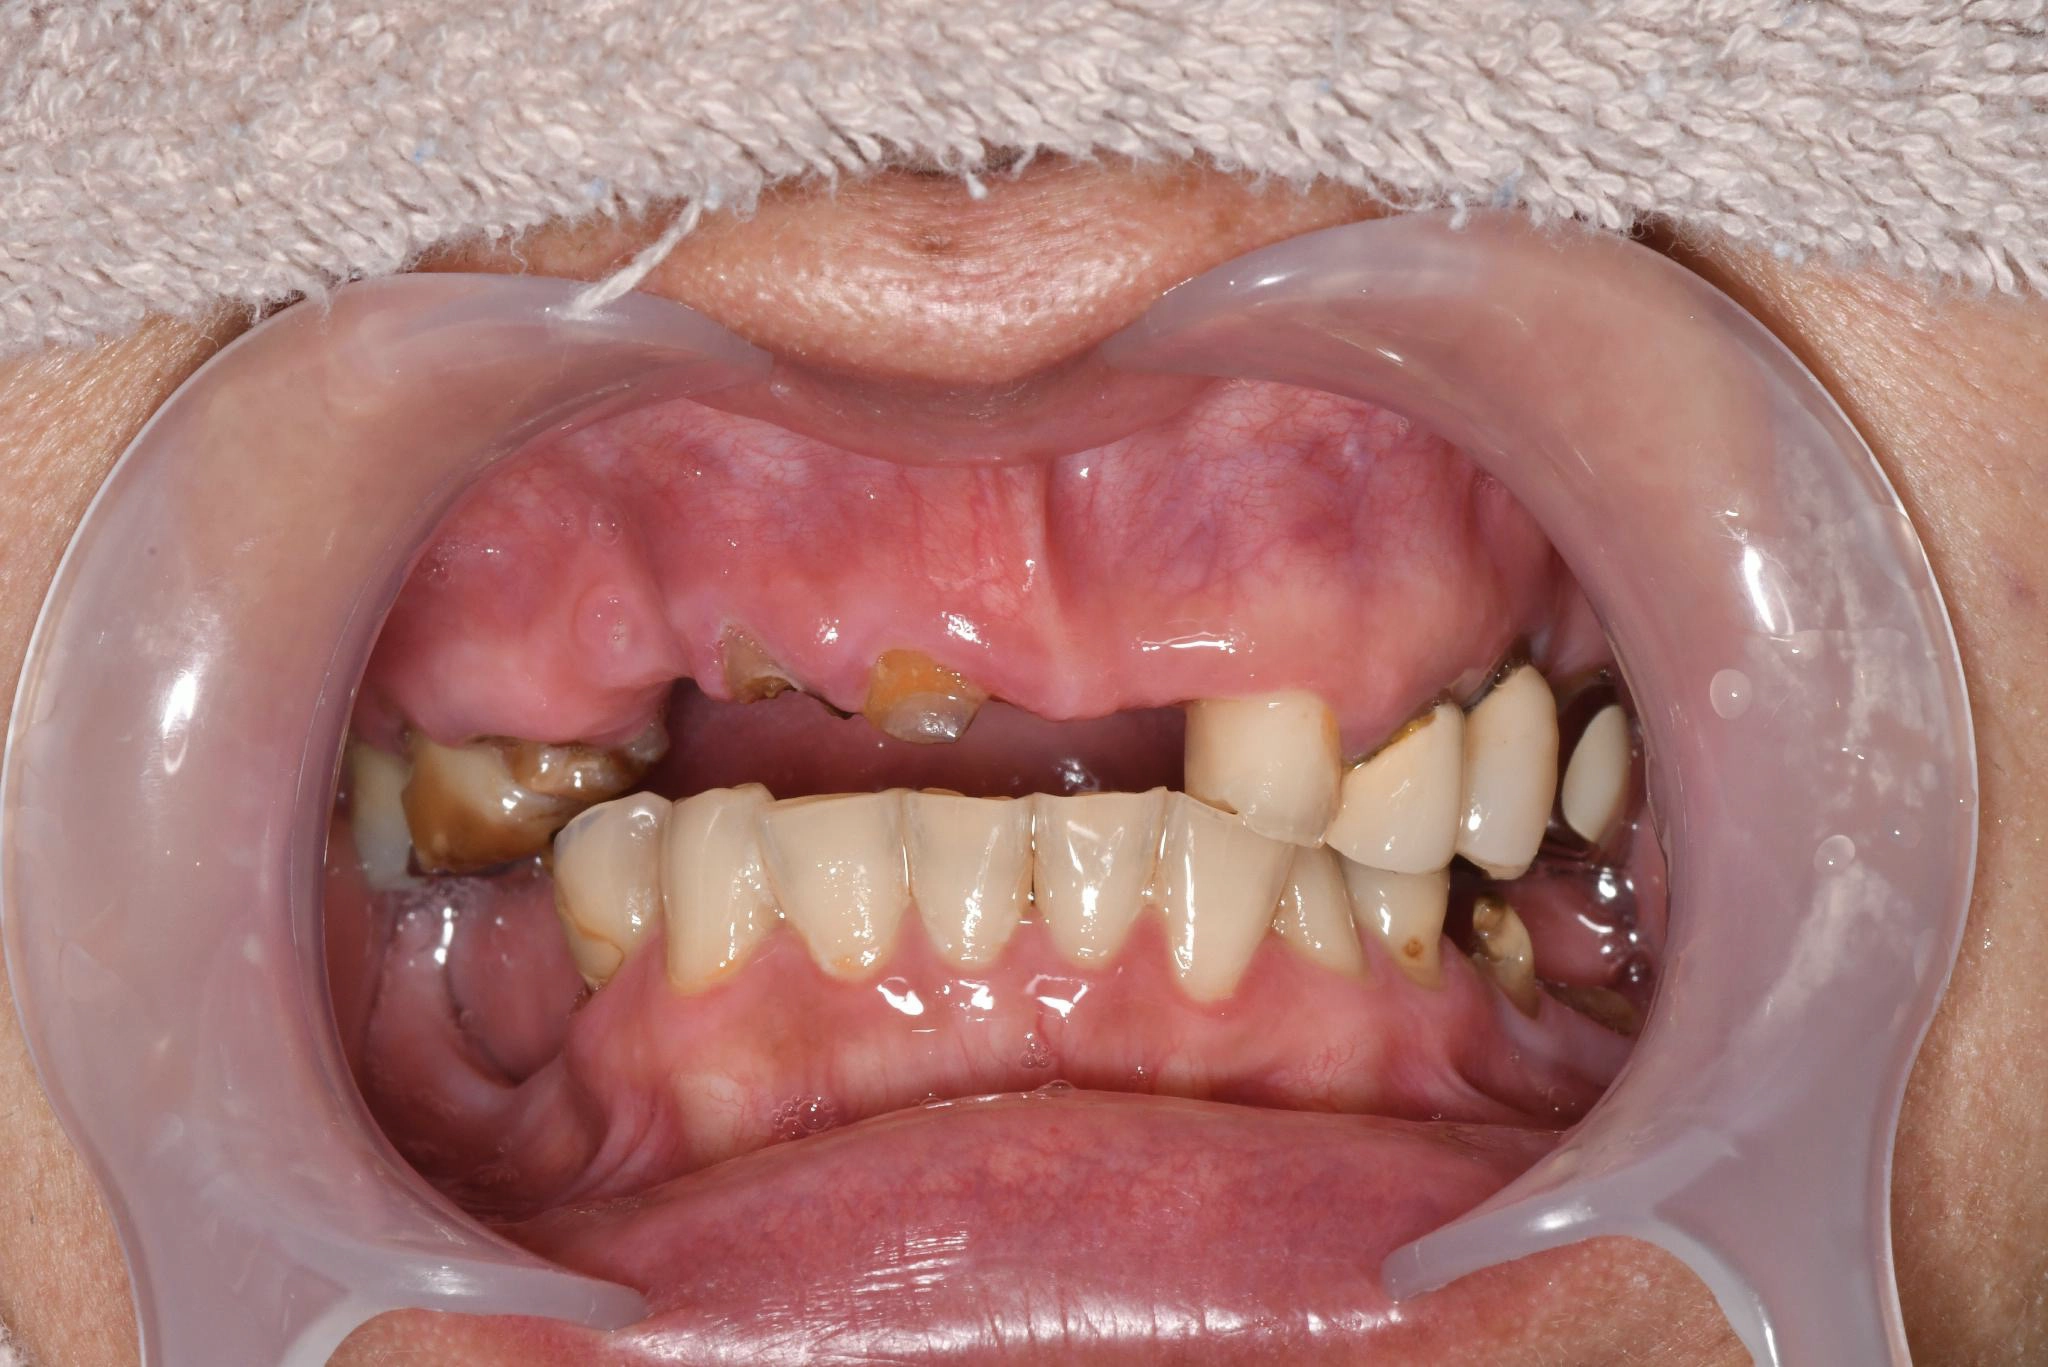

術前

長年歯について悩んでいました。歯がぐらつくことがあり、治療を行っていました。他院で入れ歯を作りましたが、噛み合わせが合わず、食事の際に噛みにくさを感じていました。

持病があるため、手術を受けられる状態か相談しに行くことにしました。

話を聞いてみるとスッタッフの方が親切で、不安な部分を確認しながら相談できました。

術中は特に痛みを感じることはなく、気づいたらいつの間にか終わっていました。術後、これまでの歯の状態と比べて綺麗になっていてとても満足しています。